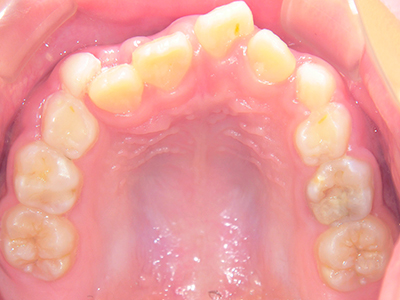

歯並びの相談に来られるお子様は、口呼吸をしているケースが多く、これが歯並びに大きな影響を与えています。

↓ - さまざまな不正咬合が生じる

ないき歯科クリニックでは、上あごの成長不足を補い、鼻呼吸を獲得しつつ歯列を整え、将来のお口をより健康な状態にすることをゴールに定める矯正治療をおこなっています。